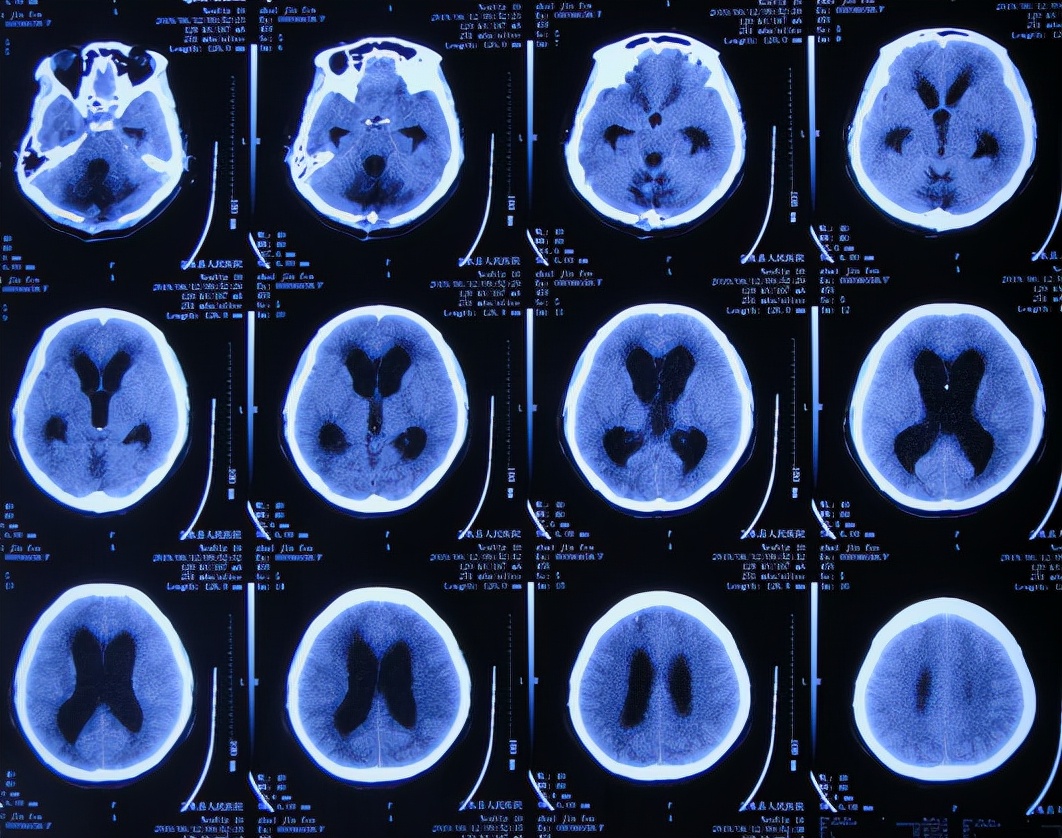

脑出血脑室外引流术后2周,为防止发生颅内感染拔除了脑室外引流管。脑出血脑室外引流术后20天,意识再次变差浅昏迷,为进一步治疗于脑出血后21天即2019年3月11日(拔除脑室外引流后1周)转至第2家的上级的山西省某省级的三甲医院;入院后查头颅核磁示脑积水( 图-7 )。

图-7: 2019年3月11日头颅核磁

住院10天左右的时间内给予腰穿3次,脑脊液培养均无菌生长,期间2019年3月19日查头颅CT示仍脑积水( 图-10 )。

图-10: 2019年3月19日头颅CT

在第3家医院住院大约64天时间内,期间(2019年3月29日、2019年4月28日)查头颅CT虽均示脑室扩张( 图-11、图-12) 。

图-11: 2019年3月29日头颅CT

图-12: 2019年4月28日头颅CT

2019年6月11日(出院后27天),走路仍不好,且出现头部、后颈、双肩、双上肢疼痛,睡觉时有尿*禁失**,于2019年6月12日第2次就诊于当地的第1家的山西省文水县某医院,查头颅CT示脑积水加重( 图-13 ),医生看到病人病情反复,建议先手术试试。

图-13: 2019年6月12日头颅CT

病人和家属无奈只好于2019年6月17日(脑出血后109天),第2次就诊于上级的第2家的山西省省级某三甲医院的神经外科,查核磁( 图-14、图-15 )后建议直接进行脑室腹腔分流术。

图-14: 2019年6月17日核磁

图-15: 2019年6月17日核磁